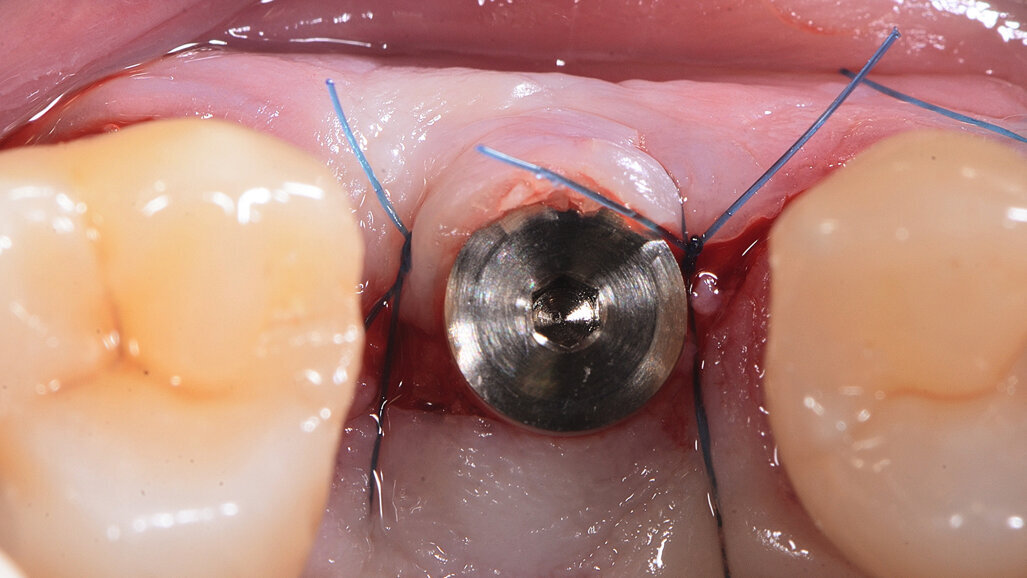

Fig. 17: Pose de l’implant deux pièces en céramique au niveau tissulaire.

Fig. 18 : Pose de l’implant deux pièces en céramique au niveau tissulaire.

Fig. 19 : Pose de l’implant deux pièces en céramique au niveau tissulaire.

La pose immédiate d’un implant deux pièces en céramique au niveau tissulaire a été accomplie tout en préservant l’alvéole (allogreffe constituée d’un substitut osseux et protection par une membrane de collagène résorbable). La mise en charge n’a pas été réalisée à ce stade (Figs. 12–24)